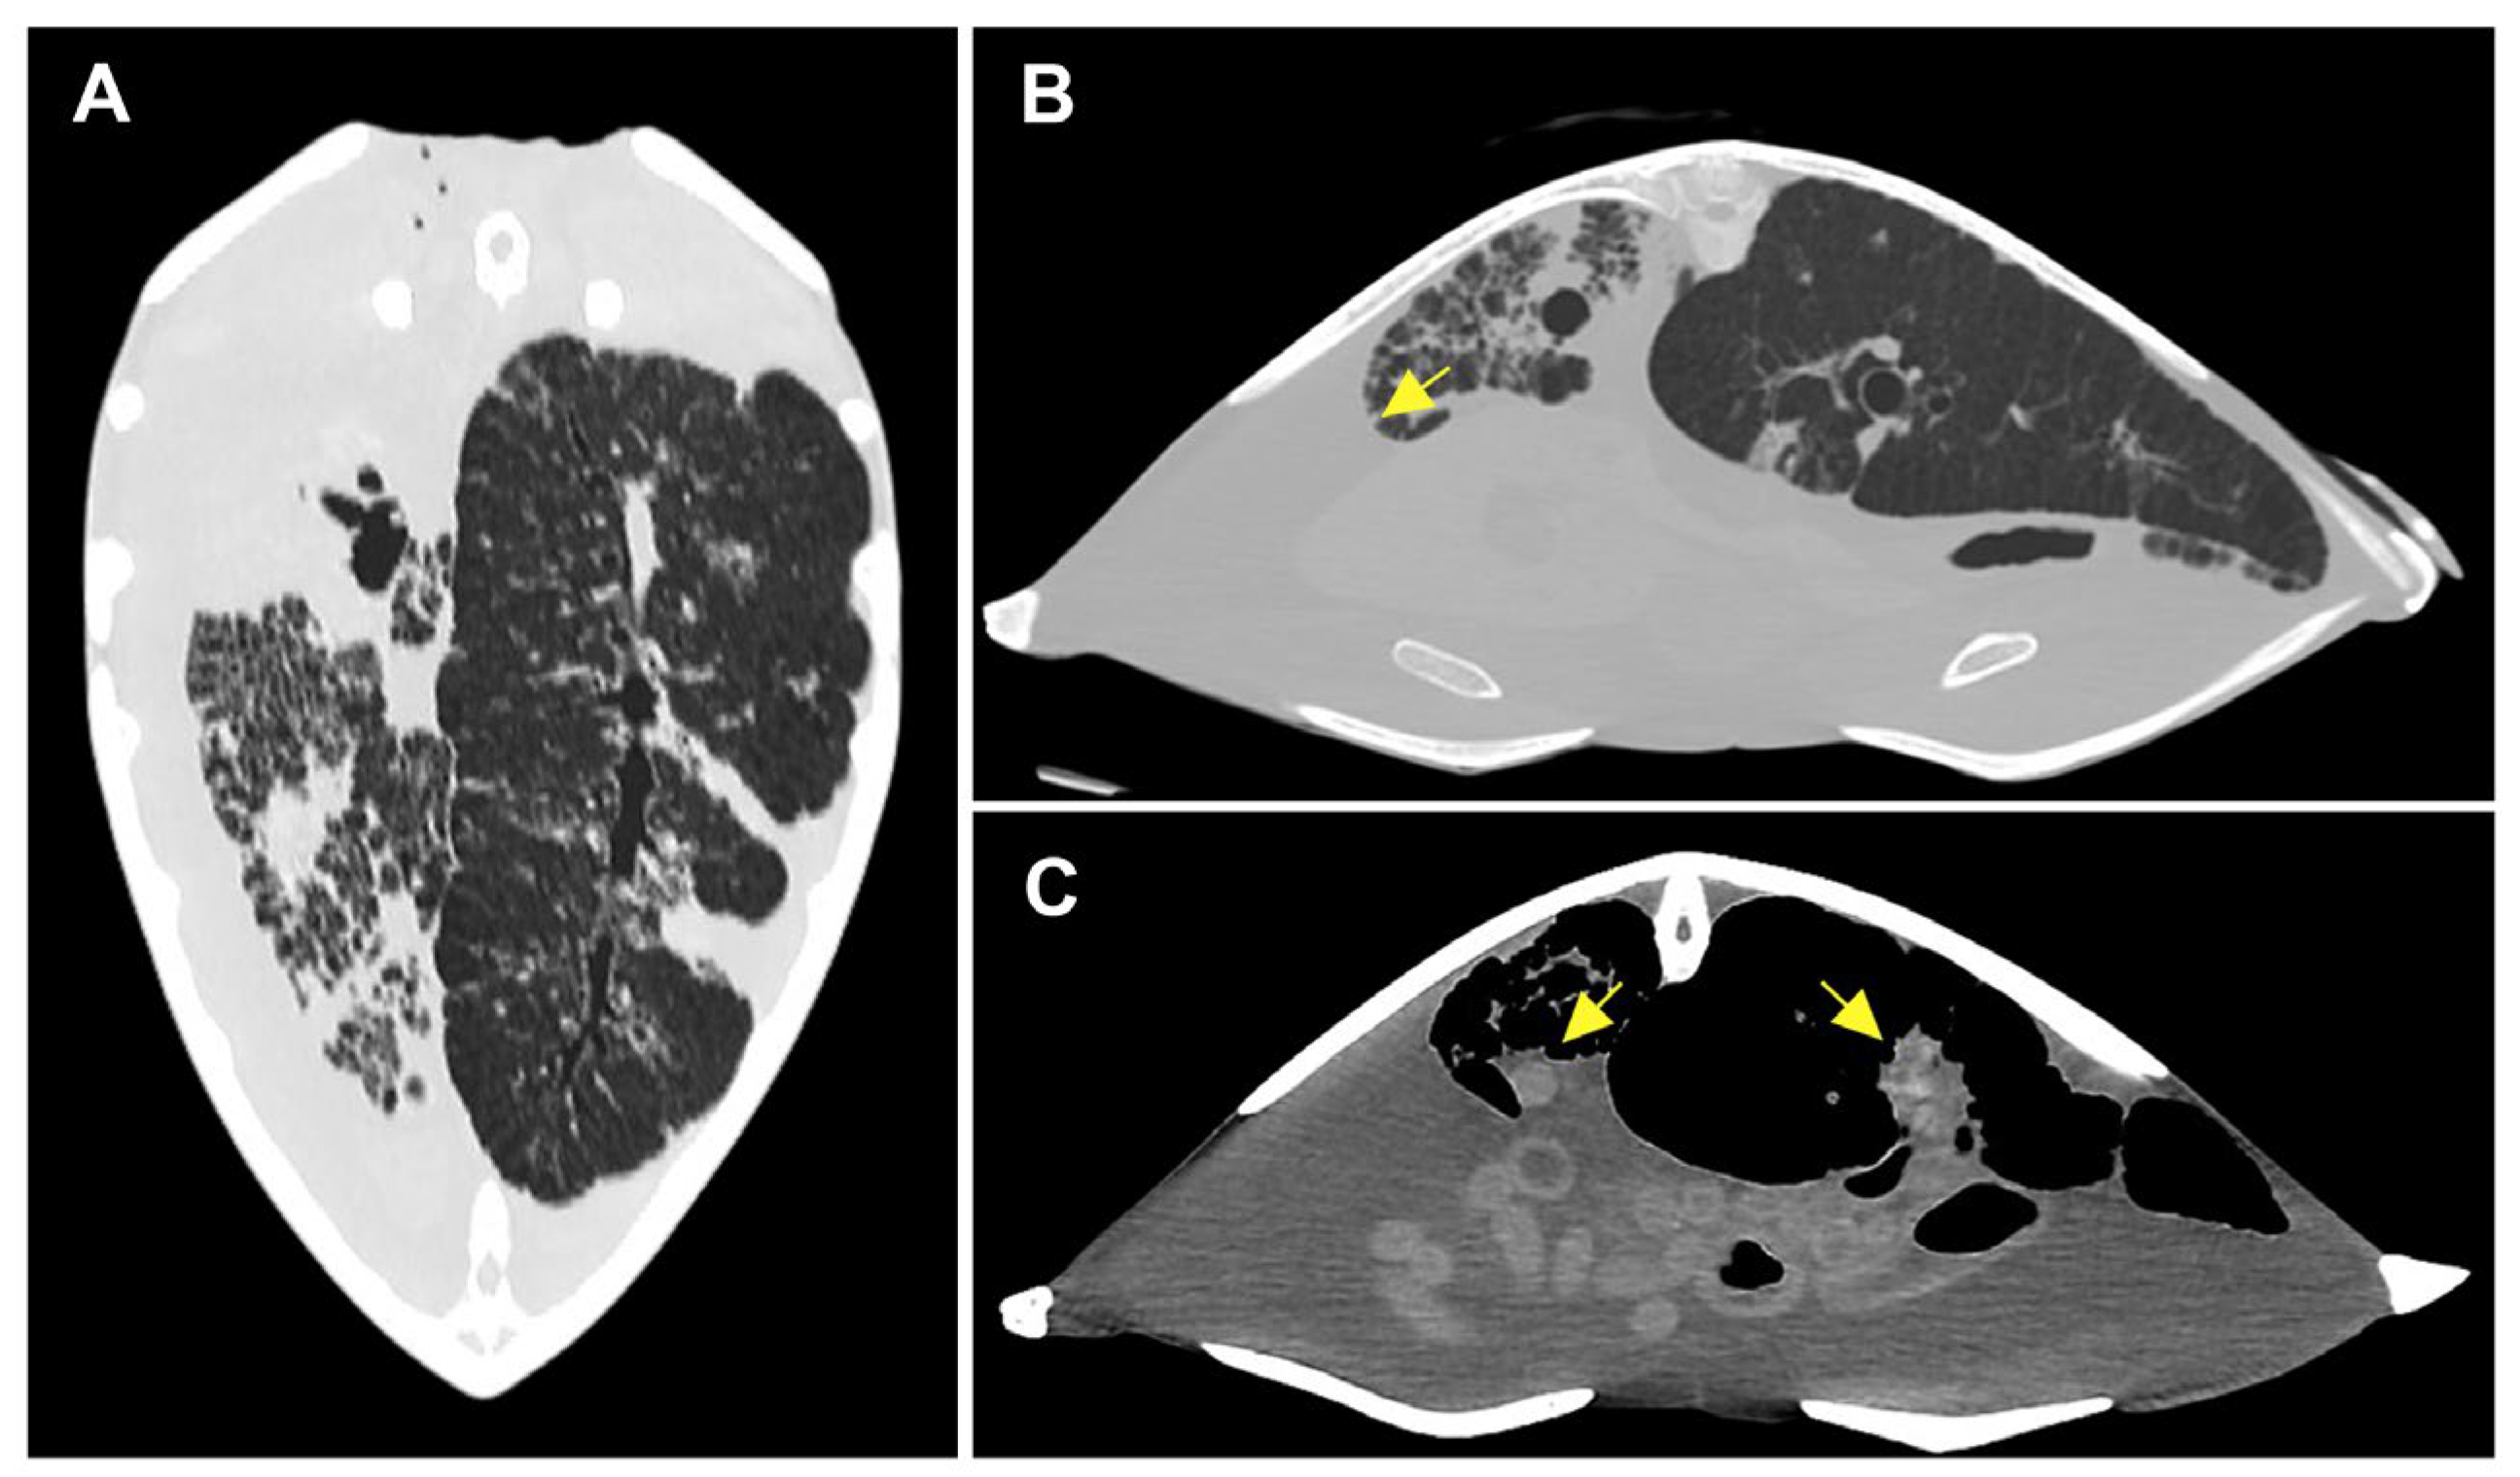

3.1.2. Radiological Findings

3.2. Postmortem Examination